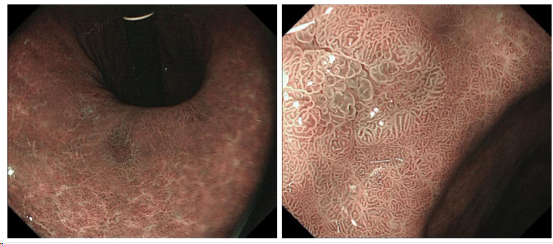

如图是一位53岁男性萎缩性胃炎患者(除菌后3年)。脾胃病科门诊医生推荐行麻醉胃镜,患者开始犹豫,经医生解释,选择麻醉胃镜精查;操作者按白光观察流程扫查胃窦、胃角小弯,发现粘膜薄、多发红色区。

扫除胃角近后壁时发现蛛丝马迹,见一处可疑病灶(色调异常)。若是无麻醉情况下,多数因患者无法耐受出现呕吐,导致胃腔变小,病灶观察不到。

高清内镜切换成电子观察,发现病灶(茶褐色,边界清楚),经电子放大下明确胃早癌;后续经胃镜下微创切除(ESD术),病理符合早期胃癌。